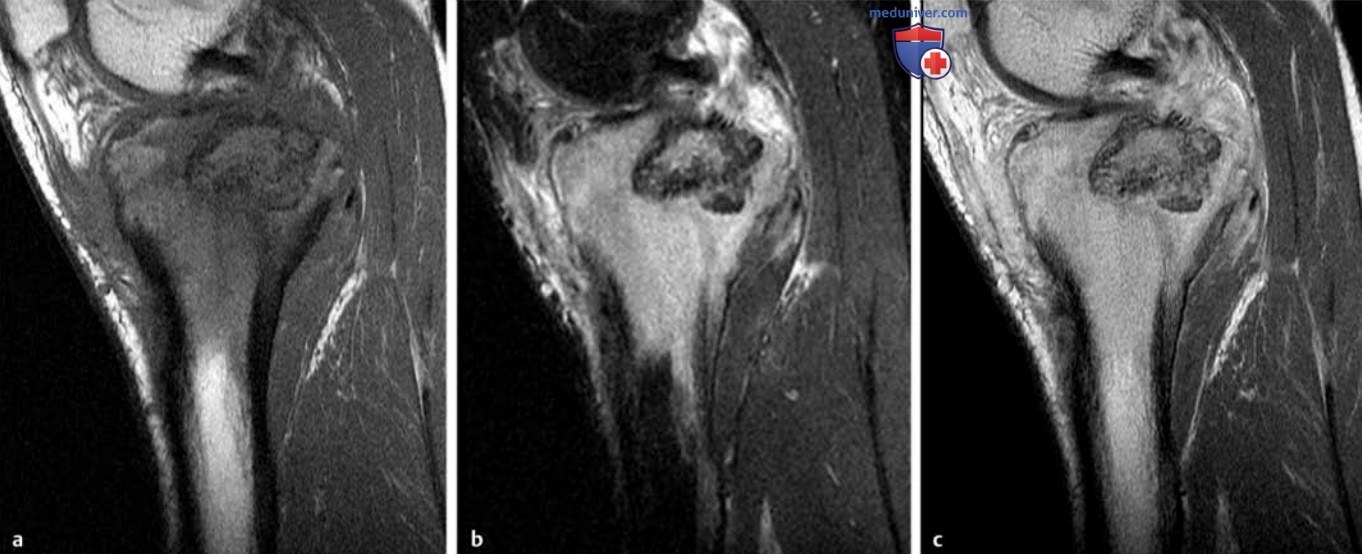

Рисунок 9. a-c Гигантоклеточная опухоль проксимального суставного конца большеберцовой кости.

а Т1в-SЕ-изображение во фронтальной плоскости.

b Т2в-ТSЕ-изображение во фронтальной плоскости.

c Т1 B-SE-изображение после контрастирования.

Визуализирована опухоль проксимального конца большеберцовой кости с гетерогенной интенсивностью сигнала при всех ИП. Поражение распространяется до субхондральной костной пластинки, пенетрирует кортикальный слой по медиальной поверхности и имеет небольшой экстраоссальный компонент. Распространенные отложения гемосидерина объясняют очень низкую интенсивность Т2в-сигнала от опухолевой ткани.